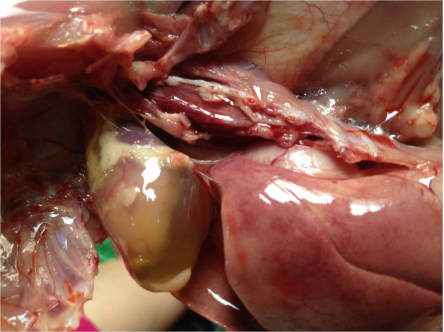

以心包積液、出血性肝炎為特征,發病急、傳播快,發病家禽的特征性癥狀是無明顯先兆而突然倒地,兩腳劃空,數分鐘內死亡。其剖檢變化主要為死亡家禽有明顯的心包積水,心包呈水囊狀;肝臟腫大、質脆且充血,外觀呈淺黃至深黃色,肺臟淤血水腫。